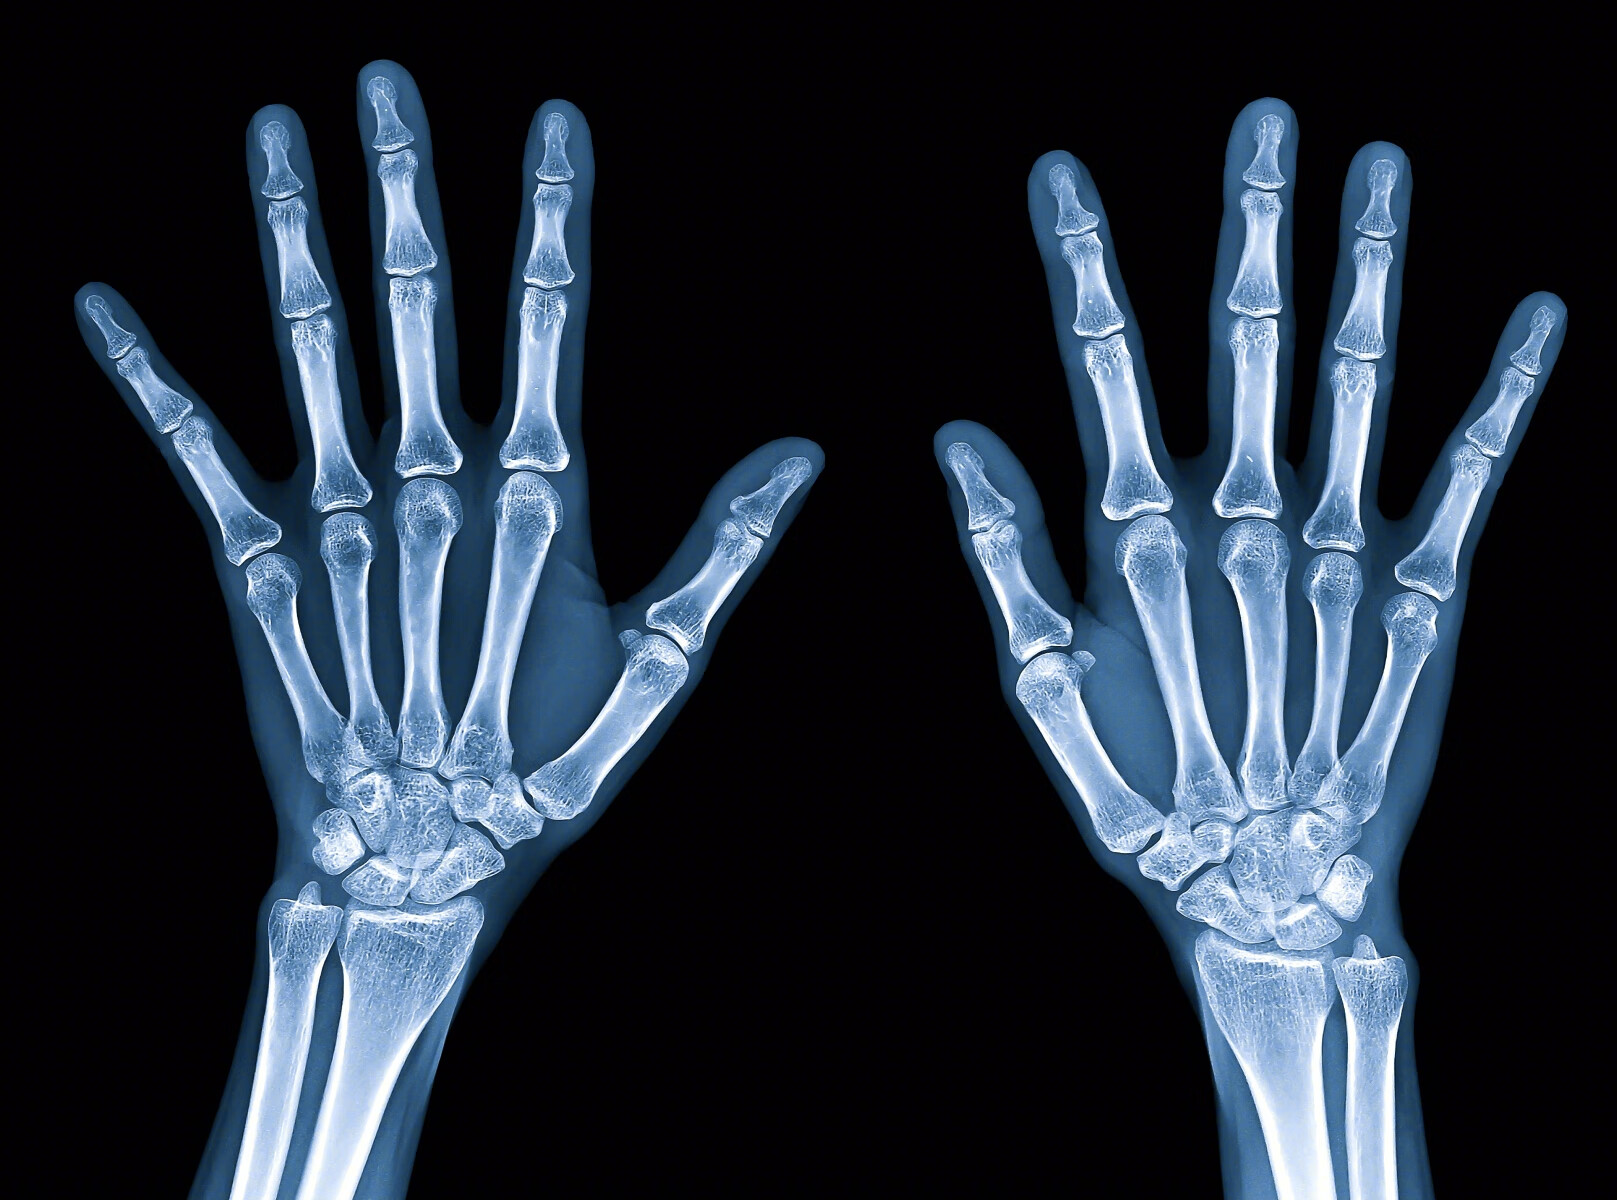

腕管综合征是一种常见的影响腕部和手部神经的疾病,因其名称来源于控制腕部和手部感觉和运动的中枢神经,中枢神经会穿过腕部的一段称为“腕管”的区域。由于正中神经局限于腕骨和腕腱之间,手部和腕部会感觉到麻木和刺痛,或手腕和上臂会感觉到强烈的刺痛感。

对于办公室工作人员来说,腕部疼痛是一种习惯,由于过多地使用键盘和鼠标,很容易造成腕部疼痛和手脚麻木,这就是腕部疼痛的症状,腕部疼痛是腕部的一种症状,它是肌腱与正中神经相连,当肌腱肿起来压迫正中神经时,就会引发腕部疼痛。中枢神经的作用是控制拇指、食指、中指和无名指的运动,当受到损伤或压迫时,会感觉麻木、无力和疼痛。

医生可以借由敲击腕部的中段神经,弯曲腕部,并让中段神经保持一个固定的姿势几秒钟,以检查腕部状态,评估疼痛的程度,医生还可以要求进行其他测试,以确定腕部神经和肌肉的状态。